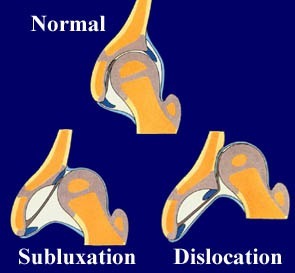

Η αναπτυξιακή δυσπλασία ισχίου είναι μια σοβαρή παθολογία κατά την οποία η κεφαλή του μηριαίου δεν βρίσκεται στη φυσιολογική της θέση στην κοτύλη της λεκάνης. Αποτελεί φάσμα παθολογίας, από μικρή δυσπλασία στην κοτύλης, έως και πλήρες εξάρθρημα της κεφαλής του μηριαίου. Το ποσοστό εμφάνισης αναπτυξιακής δυσπλασίας του ισχίου αντιστοιχεί περίπου στο ένα βρέφος ανά χίλιες γεννήσεις.